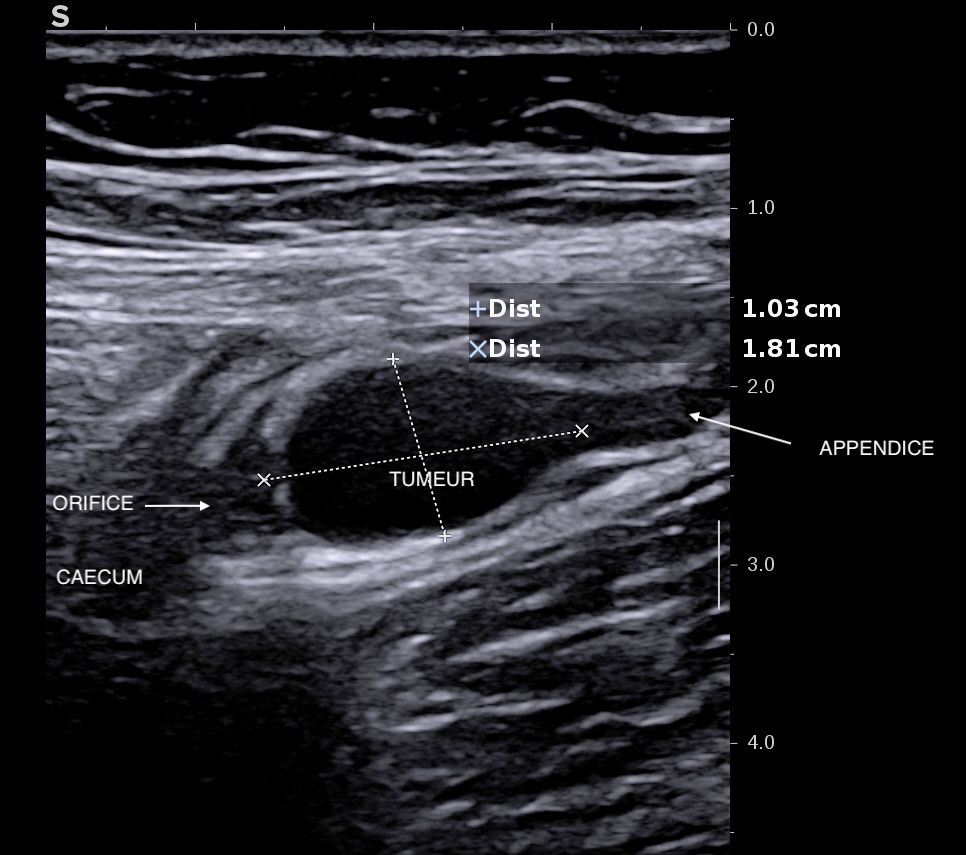

En échographie, à distance (éviter le jour de la coloscopie car l'air peut masquer les images), on voit parfaitement les lésions au delà de l'orifice appendiculaire, la tumeur fait 18 mm x 10 mm et l'appendice au delà est rempli de mucus.